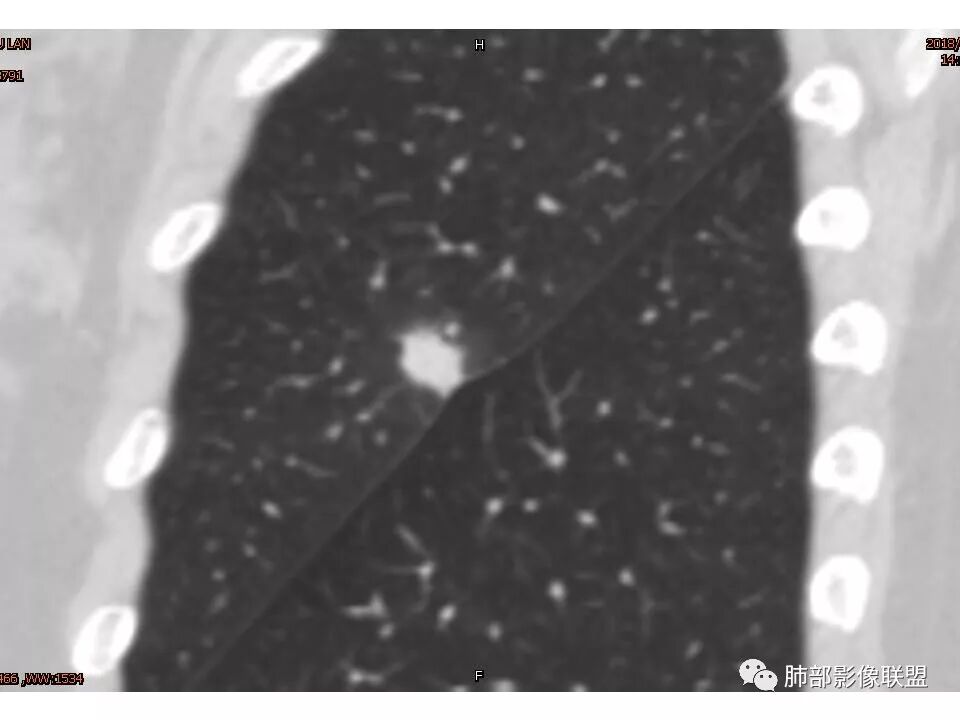

女性,50岁。U型凹陷、平直征

南边:支持炎性

这些层面不大放心

南边 :

我倾向于炎性结节,癌待排

1.胸膜下略不规则实性密度结节影,孤立,缺乏典型深分叶,可见淡薄边界模糊磨玻璃晕,可见相对细长软毛刺。

2.如南边老师分析,病灶缺乏边缘膨隆优势,甚至部分平直内收。

3.病灶收缩力不强,整体强化程度不显著。

4.综上,病灶更符合炎性,如隐球菌感染等,而不大符合肺腺癌。具体到机化性肺炎略有些出乎预料。